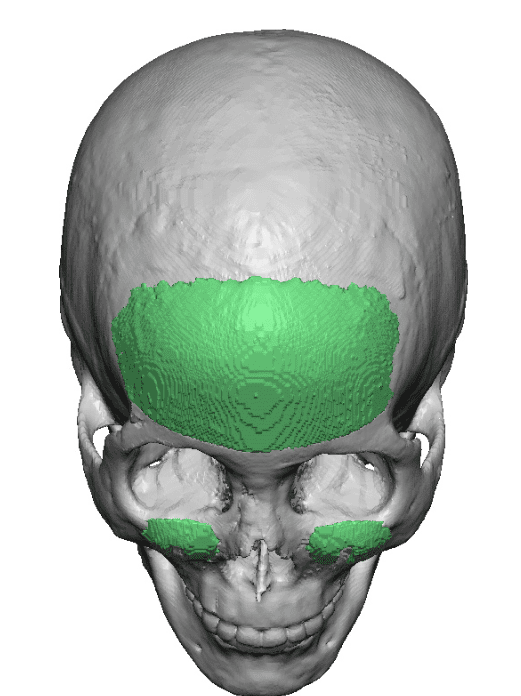

Patient 110

Desire for head shape asymmetry improvement as the final stage of total skull reshaping surgeries. (previous skull implants are in green color)

Placement of custom temporal implant through an incision behind the ear.

Desire for head shape asymmetry improvement as the final stage of total skull reshaping surgeries. (previous skull implants are in green color)

Placement of custom temporal implant through an incision behind the ear.